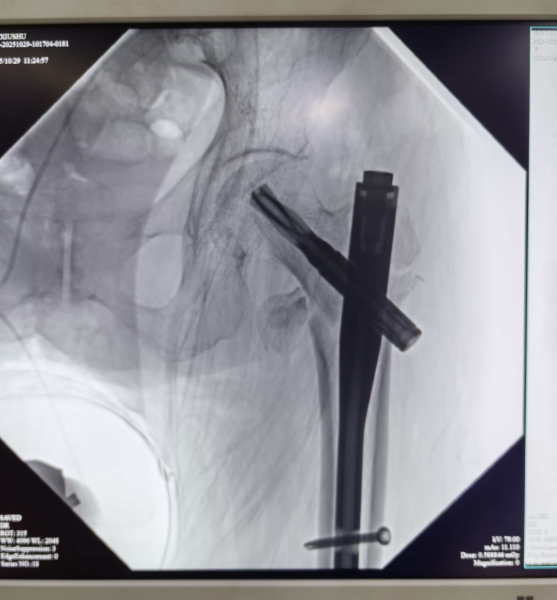

手术当天,各科室团队提前到位,骨外科主刀医生凭借精湛技术,在影像设备引导下精准定位骨折部位,通过微小切口完成复位与固定操作,出血量不足50毫升;手术麻醉科团队全程严密监测老人的心率、血压、血氧饱和度等生命体征。